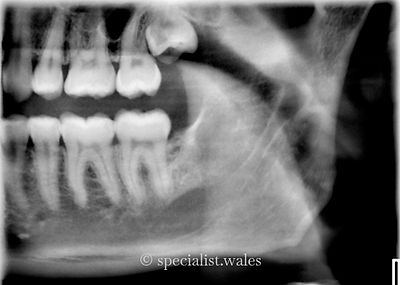

Teeth need removing for many different reasons, but sometimes it can be because there is a cyst related to the tooth. Cysts can also develop in the jaw where a tooth has been previously extracted. Management of a cyst is usually by careful surgical removal. We then send the cyst of to a pathologist for them to provide an exact diagnosis as to the type of cyst that it was. Different cysts have different long-term management as some types of cysts may be prone to recurrence whereas for most they do not recur. Our team of oral surgeons have thousands of hours of operating experience which enables them to approach cysts in careful and efficient manner for their patients. This helps to reduce procedure time and trauma as well as decreasing the risk of complications during or after surgery.